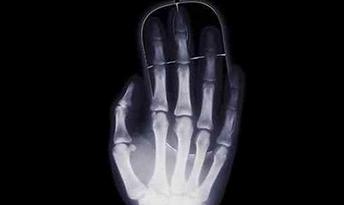

3D打印在醫(yī)療領域的進步是一個全球化的現(xiàn)象。世界各地的醫(yī)生將3D打印與手術相結合,科學家們也以驚人的速度研究生物3D打印,毫無疑問,未來的醫(yī)學世界必將會被3D打...